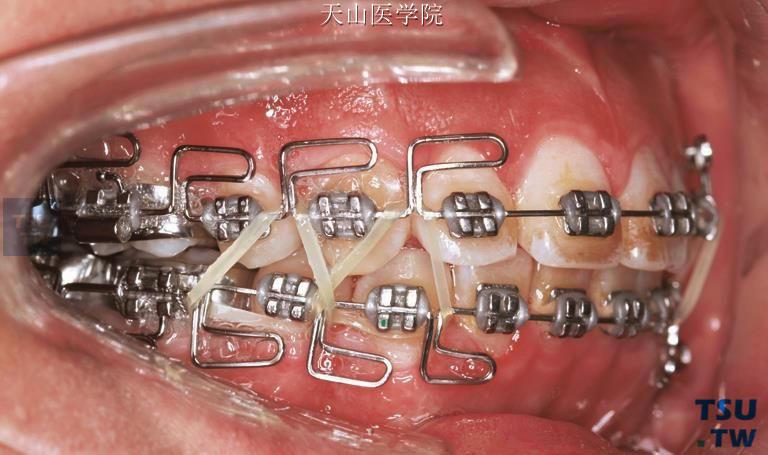

- 联合牵引:根据病例类型配合颌间牵引(如III类牵引垂直牵引),增强矫治效果;

水平曲用于调整牙齿的转矩和近远中倾斜,通常在垂直曲的龈方弯制:

- 角度:与垂直曲成90°,水平臂与牙合平面呈120°-140°角(后牙区角度略大,前牙区略小);

- 长度:水平臂长度为4-5mm,末端回弯1-2mm形成小钩,便于结扎或牵引;

- 弯制要点:用细丝弯钳夹住垂直曲龈方,向颊舌向弯制水平曲,确保角度一致,避免应力集中导致弓丝折断。